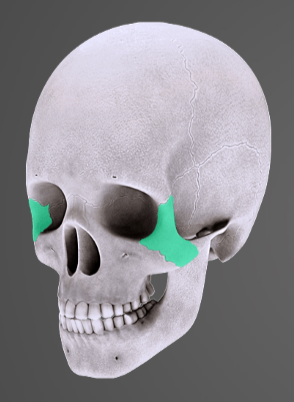

Co z uvedeného je zeleně vyznačeno?

průdušnice

průdušky

nosohltan

hrtan